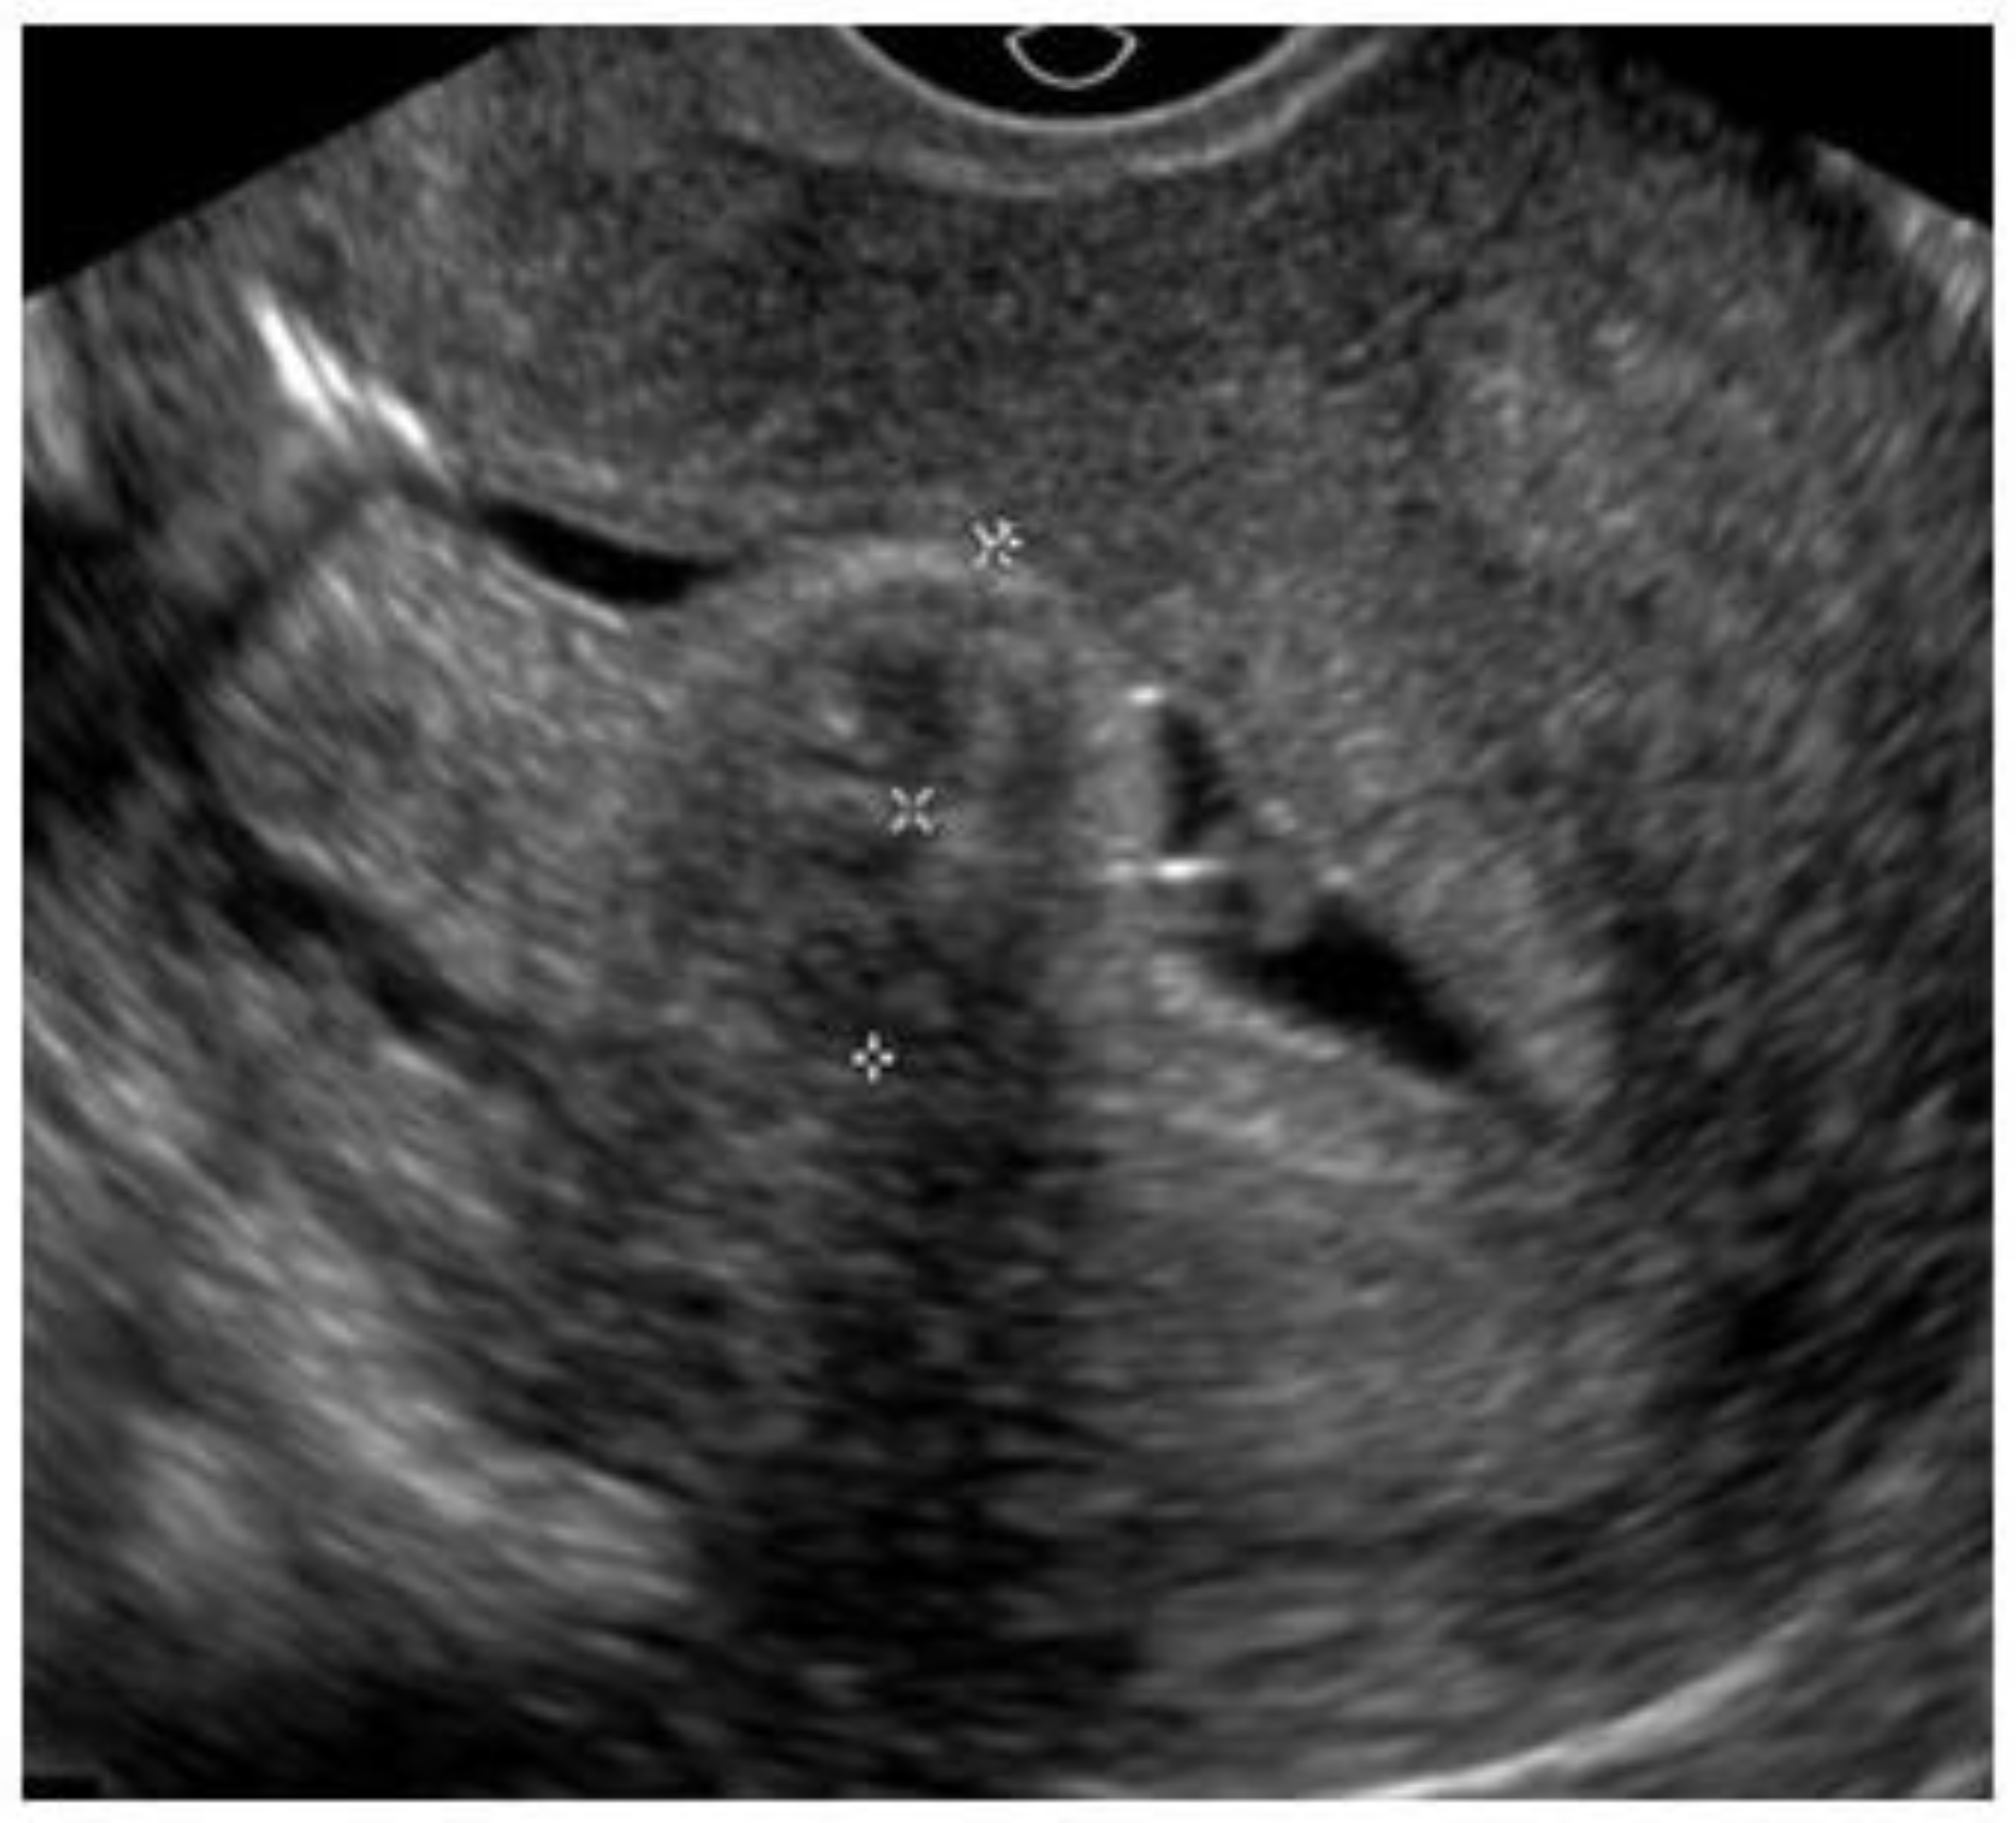

3.1. Hysteroscopic Myomectomy Techniques

Myomectomy, whether laparotomic or laparoscopic, is a well-established procedure, widely performed with the goal of uterine preservation. In both approaches, the myomectomy technique is the same: incision of the serosa up to the pseudocapsule, identification of the myoma, traction and movement of the nodule, assistance in dissecting the plane of the pseudocapsule within the myometrium, and enucleation of the myoma from the uterine wall. This fibroid enucleation technique is known and performed by all gynecologists. When the pseudocapsule is reached, the chance of preserving the uterus will be greater, with less bleeding and less myometrial damage, which differs from adenomyosis resection, which does not have a pseudocapsule [21] (Figure 6).

Figure 6. Laparotomic and laparoscopic myomectomy preserving pseudocapsule.